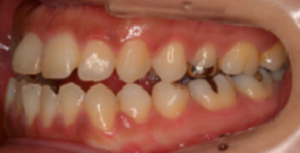

歯周病が進行し、グラグラして物が嚙めず、抜歯してインプラントにしていくことに。

インプラントはストローマンを使用、上部構造はジルコニアセラミックス